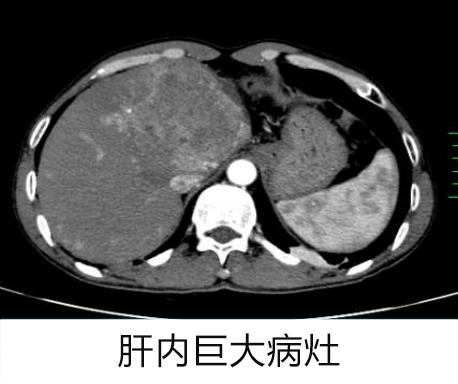

这位 51 岁的男性患者,因右上腹胀痛 1 周于 2022 年 7 月来到罗湖区人民医院就诊。患者既往有慢性乙型病毒性肝炎病史,入院查体显示:全身皮肤巩膜无黄染,腹平软,上腹部轻度压痛。经 CT 检查,发现 肝脏左叶肿瘤性病变,伴肝内多发转移灶。

实验室检查结果显示,AFP 指标高达 31623ng/mL。肝脏穿刺活检结果确认为 肝细胞性肝癌(中分化)

1. 肝癌并肝内多发转移(CNLC-Ⅱb)